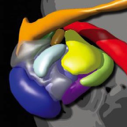

Amygdala Subdivision Atlas

The Caltech Conte Center for the Neurobiology of Social Decision Making has constructed a probabilistic atlas of the human amygdala based on 168 neurotypical adults from the Human Connectome Project S500 data release. The atlas and associated templates are available for download as an open and evolving resource for future functional and structural imaging studies of the human amygdala. [ Collaboration with Wolfgang Pauli ]